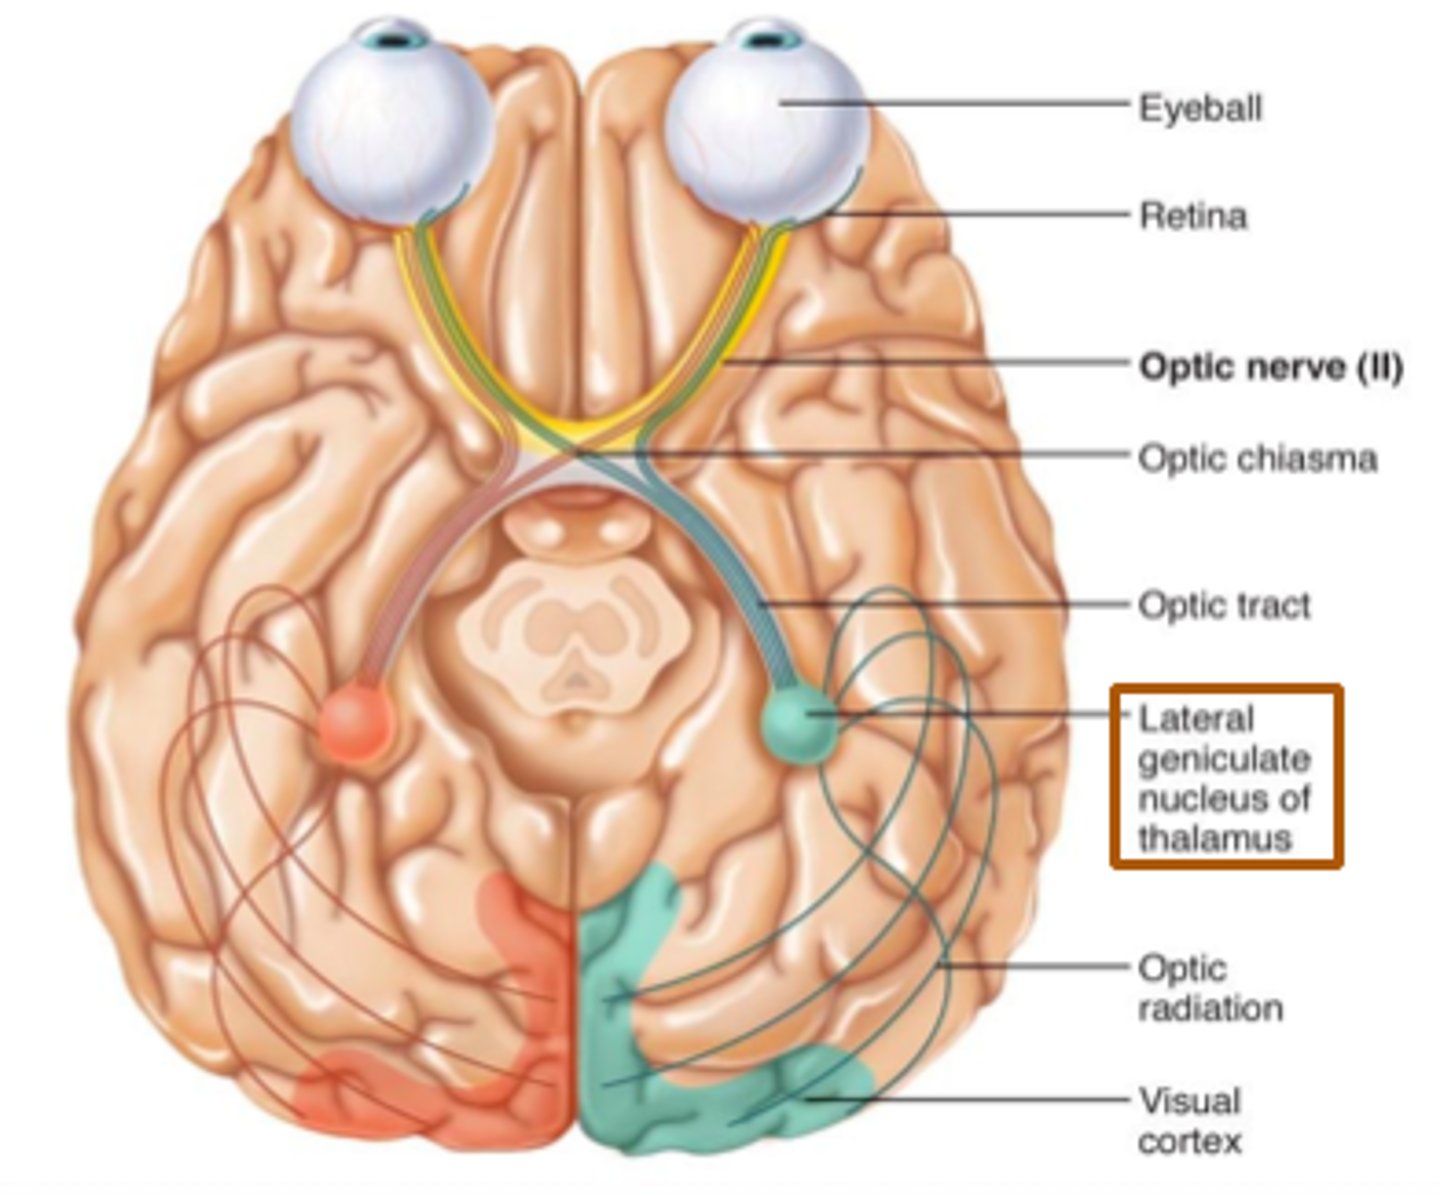

optic nerves (II)

Includes optic chiasma and optic tract. The X

optic chiasma

portions of visual fields from both of eyes that cross here. Crossing over of information.

optic tract

bottom legs of the X. Goes to myelinated axons in CNS. This information should go to thalamus. It will go to occipital lobe.